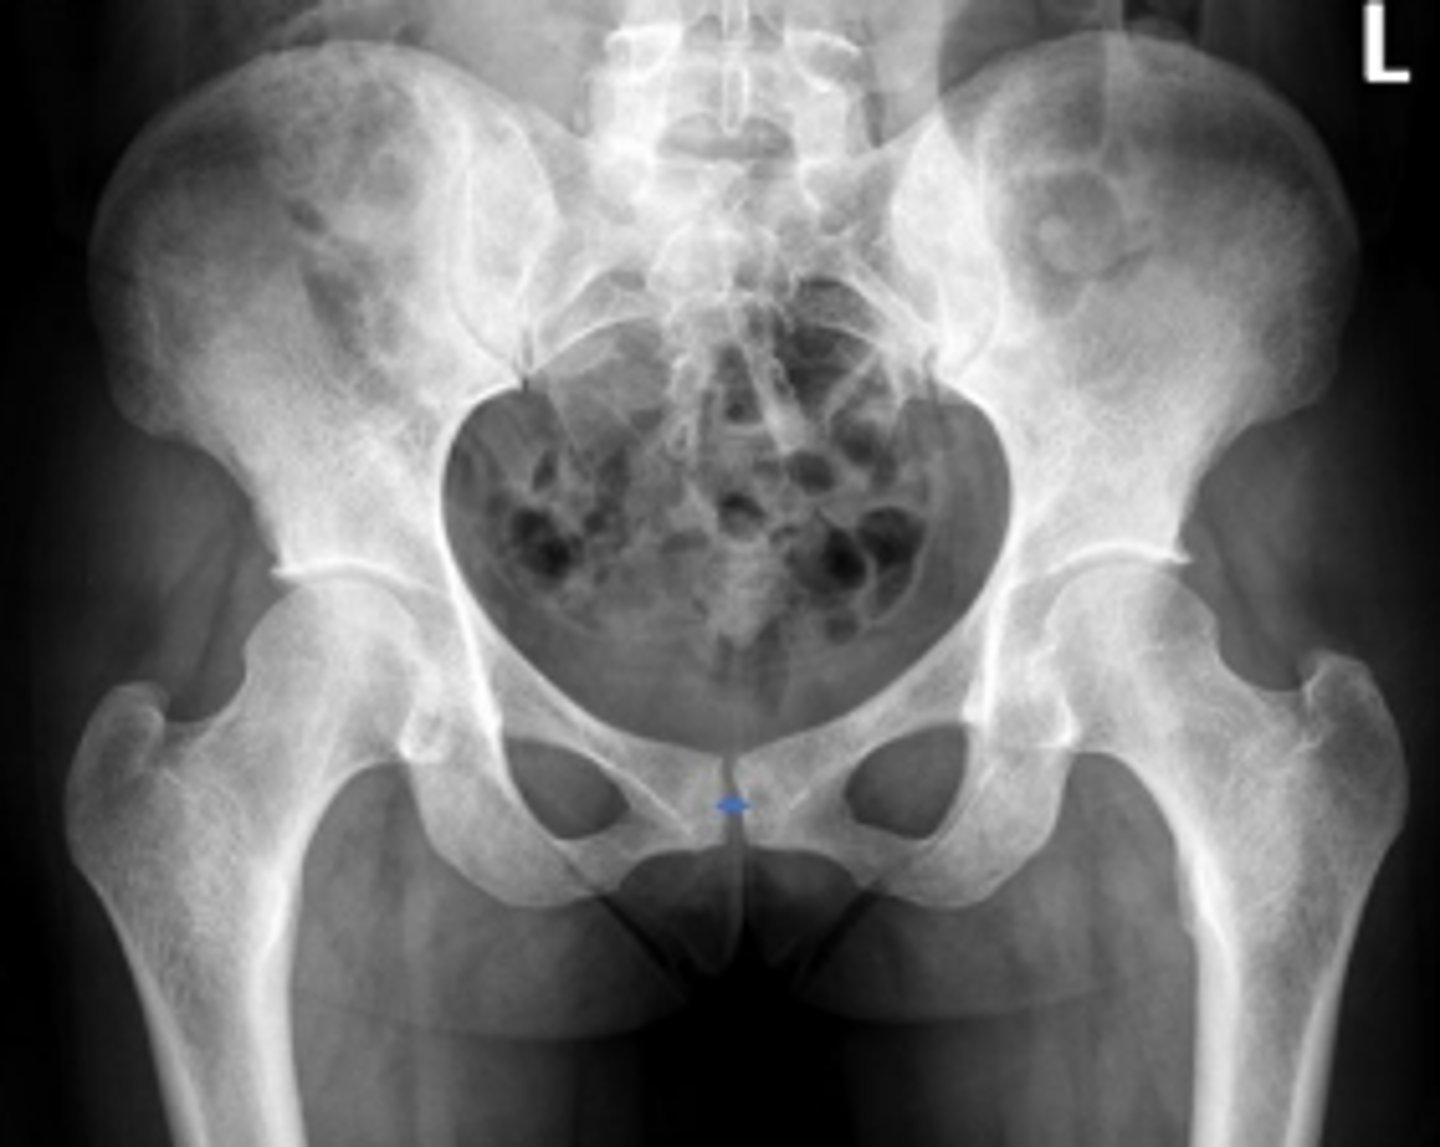

Right iliopectineal line

What is the name of the assessment?

Right ilioischial line

Center edge angle

20-40 degrees

What is the normal range for this assessment?

A vertical line is drawn upwards from the center

of the head of the femur.

The second line is drawn from the center of the femur head to the outer superior-lateral aspect of the acetabulum

What are the osseous landmarks for this assessment

No (normal measurement is 20-40 degrees)

Is the measurement within normal limits?

Acetabular dysplasia

Developmental dysplasia of the hip

Name 1 condition that may result in a measurement <20 degrees?

AP pelvis and AP hip views

Name 2 radiographic views for this assessment?

A mechanical instability of the femoroacetabular

joint characterized by a shallow acetabulum

providing insufficient covering of the femoral

head

What is developmental hip dysplasia?

Teardrop distance

6-11mm

The distance between the most medial margin of

the femoral head and the adjacent pelvic

teardrop

What are the osseous landmarks for this assessment?

Yes (normal is 6-11mm)

Femoroacetabular joint inflammation

Name 1 condition that may result in a measurement of 15mm?

Late stage degenerative joint disease

Protrusio acetabuli

Name 2 conditions that may result in a measurement of 3mm?

Waldenstrom's sign

What is the named sign if this assessment has a value > 2mm difference

between the left and right side?

Hip joint space width

Superior joint space is 3-6mm

Axial joint space is 3-7mm

Medial joint space is 4-13mm

Superior joint space-> The measurement between the most convex superior aspect of the femoral head and the adjacent acetabulum

Axial joint space -> The measurement between the

femoral head and the acetabulum lateral to the

acetabular notch

Medial Joint space -> The measurement between the most medial margin of the femoral head and the adjacent pelvic teardrop

Yes

Are the measurements within normal limits?

Degenerative joint disease

Name 1 condition that may result in a measurement of <3mm for the superior joint space?

Shenton's line

From the undersurface of the femoral neck

continued to the inferior aspect of the superior

pubic ramus

What are the osseous land marks for this assessment?

Hip dislocation, fracture

Name 2 conditions that may result in an abnormal assessment?

Posterior hip dislocation

What is most significant radiographic finding?

Femoral angle

120-130 degrees